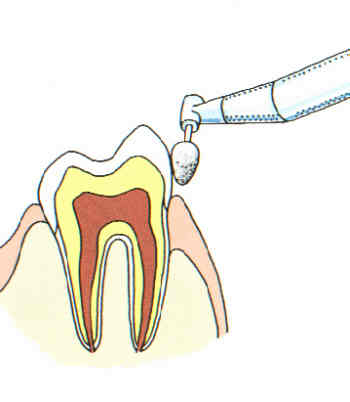

Ultraschall-Zahnsteinentfernung

Am schonendsten wird Zahnstein mit einem Ultraschallgerät entfernt. Eine Ruhigstellung ist dazu erforderlich.

Zahnpolitur

Nach der Zahnsteinentfernung werden die Zähne poliert, um neuer Zahnsteinbildung möglichst wenig Ansatzstellen zu bieten.